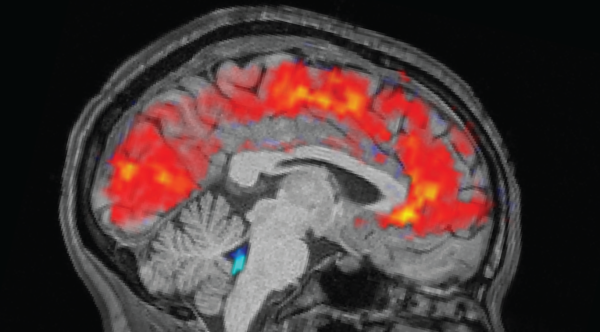

Ingesting an excessive quantity of alcohol in a solitary instance compromises the hippocampus, a cerebral area of vital significance for the establishment of memories. Resultantly, blackouts may occur, inhibiting an individual from recalling occurrences during their period of inebriation.

Upon reaching inordinately elevated levels of alcohol in the bloodstream, cerebral regions accountable for indispensable functions — notably respiration, cardiac rhythm, and alertness — likewise initiate a process of functional cessation. This phenomenon, referred to as alcohol poisoning, has the potential to induce vomiting, convulsions, a comatose state, or even mortality.